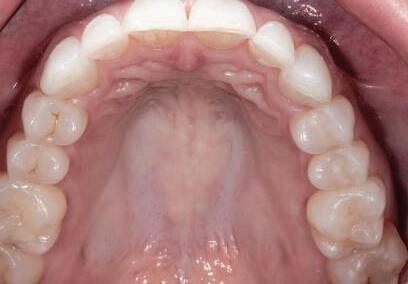

Dacă însă implanturile sunt plasate prea vestibular sau prea superficial, componentele nu permit un design adecvat al bontului, pentru că plasarea marginii este limitată iar conturul facial şi proximal poate fi compromis (fig. 1, 2).

Figurile 3, 4. Întrucât poziţia implantului era mezială faţă de ideal, bonturile individualizate s-au conceput plate pe profilul mezial, dar au prezentat provocări în privinţa conturării restauratoare. 5. Restaurările implantare de la nivelul 1.2. şi 2.2. susţin o FPD metalo-ceramică cimentată între incisivii laterali.

Figurile 1, 2. Compromisurile conturului vestibular şi proximal sunt evidente. Implantul este la nivel tisular, tehnicianul neputând gestiona plasarea marginii sau a profilului intrasulcular pentru a îmbunătăţi estetica. Dacă se concepea un design tradiţional cu hexagon extern, marginea restauratoare s-ar fi putut plasa foarte aproape de interfaţa bont-implant, cu gestionarea mai bună a spaţiului.